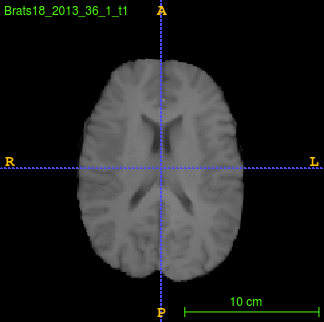

Segmentation of brain tumor from magnetic resonance imaging (MRI) is a vital process to improve diagnosis, treatment planning and to study the difference between subjects with tumor and healthy subjects. In this paper, we exploit a convolutional neural network (CNN) with hypercolumn technique to segment tumor from healthy brain tissue. Hypercolumn is the concatenation of a set of vectors which form by extracting convolutional features from multiple layers. Proposed model integrates batch normalization (BN) approach with hypercolumn. BN layers help to alleviate the internal covariate shift during stochastic gradient descent (SGD) training by zero-mean and unit variance of each mini-batch. Survival Prediction is done by first extracting features(Geometric, Fractal, and Histogram) from the segmented brain tumor data. Then, the number of days of overall survival is predicted by implementing regression on the extracted features using an artificial neural network (ANN). Our model achieves a mean dice score of 89.78%, 82.53% and 76.54% for the whole tumor, tumor core and enhancing tumor respectively in segmentation task and 67.90% in overall survival prediction task with the validation set of BraTS 2018 challenge. It obtains a mean dice accuracy of 87.315%, 77.04% and 70.22% for the whole tumor, tumor core and enhancing tumor respectively in the segmentation task and a 46.80% in overall survival prediction task in the BraTS 2018 test data set.